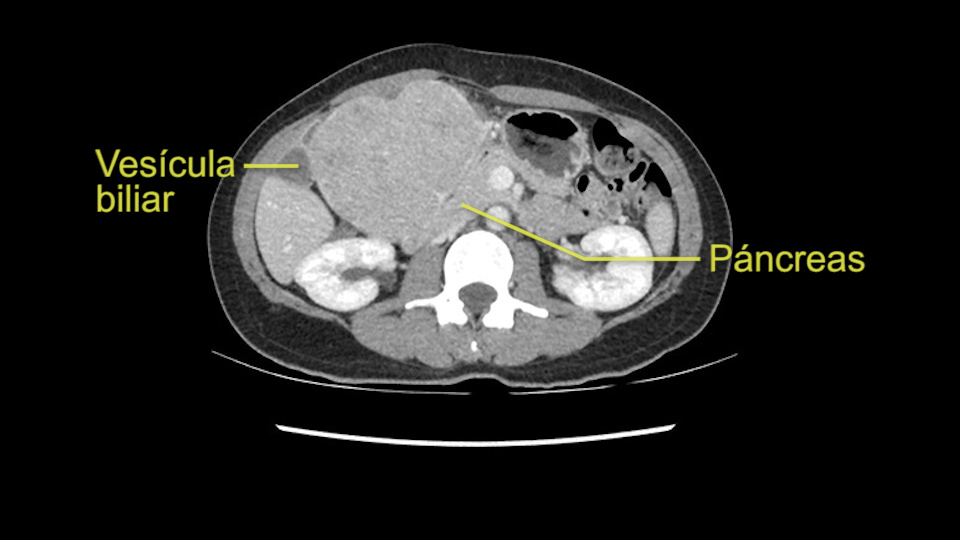

Lo siguiente que voy a hacer es mirar a la fase venosa. Y otra vez parece que todas las estructuras yendo al hígado derecho, es decir, tanto la vena porta derecha, la vena porta principal parece que están libres de tumor. Lo que si parce es que este tumor está comprimiendo diferentes estructuras, parece que comprime el páncreas, puede que este comprimiendo la cava, la vesícula biliar, pero en la mayoría de estos casos estos tumores no invaden estas estructuras, muy probablemente sea simplemente compresión, y una vez hallamos hecho la laparotomía es probable que todas estas estructuras queden separadas del tumor y puede que haya algunas adherencias que se puedan resecar sin problemas.

Compresión de estructuras